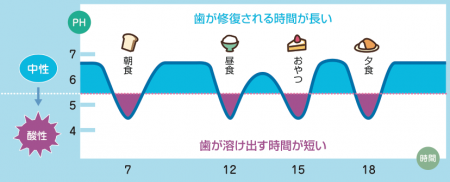

口腔内は通常は弱アルカリ性から中性(pH6.7)状態を保っており、食事をするたびに口腔内が酸性状態に傾きます。歯が溶ける境目はpH5.5以下になると言われています。

口腔内が酸性状態になると歯の表面のミネラル成分が溶かされ始めます(脱灰)。40分ほど時間が経つと唾液の自浄作用により口腔内が中性状態に戻り、溶かされた歯の成分が元に戻ろうとします(再石灰化)。そのため再石灰化をすれば歯が虫歯になることはありません

しかし、pH5.5以下の状態が長く続くような食生活を続けていると・・・

歯が溶け出す時間が長いため、歯に穴があく虫歯ができてしまいます。歯に穴があくと再石灰化することは不可能なため、歯科治療する方法しかありません

食事や間食は規則正く決まった時間にとるようにしましょう